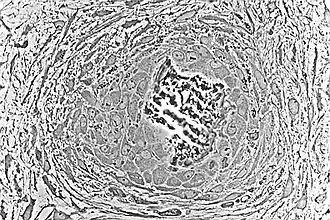

In dit stadium van ontwikkeling vinden er veranderingen plaats in de morfologie van de osteogene cellen: hun vorm wordt meer zuilvormig en de hoeveelheid Golgi-apparaat en ruw endoplasmatisch reticulum neemt toe. Uiteindelijk ontwikkelen alle cellen in de dichte cluster zich tot een osteoblast met de bijbehorende morfologische kenmerken. Vervolgens vormen de osteoblasten een osteoïd bestaande uit een extracellulaire matrix met type-I collageenfibrillen. De osteoblasten, terwijl ze de periferie van de dichte celmassa bekleden, blijven osteoïd vormen in het centrum van de dichte celmassa. Sommige osteoblasten worden opgenomen in de osteoïd om osteocyten te worden.[1]

Op dit punt wordt de osteoïd gemineraliseerd, wat resulteert in een dichte celmassa bestaande uit gemineraliseerd osteoïd dat osteocyten bevat en bekleed is met actieve osteoblasten. De dichte celmassa, dat begon als een diffuse verzameling mesenchymatische stamcellen, heeft zich ontwikkeld tot primair of gevlochten botweefsel bot, dat wordt gekenmerkt door een willekeurige organisatie van een complex netwerk van trabeculae en mechanisch zwak is, het meest primaire botweefsel.[1] Het primair of gevlochten bot onderscheidt zich duidelijk van het secundair of lamellair bot dat later bij volwassenen wordt waargenomen tijdens het bot-hermodelleringsproces.